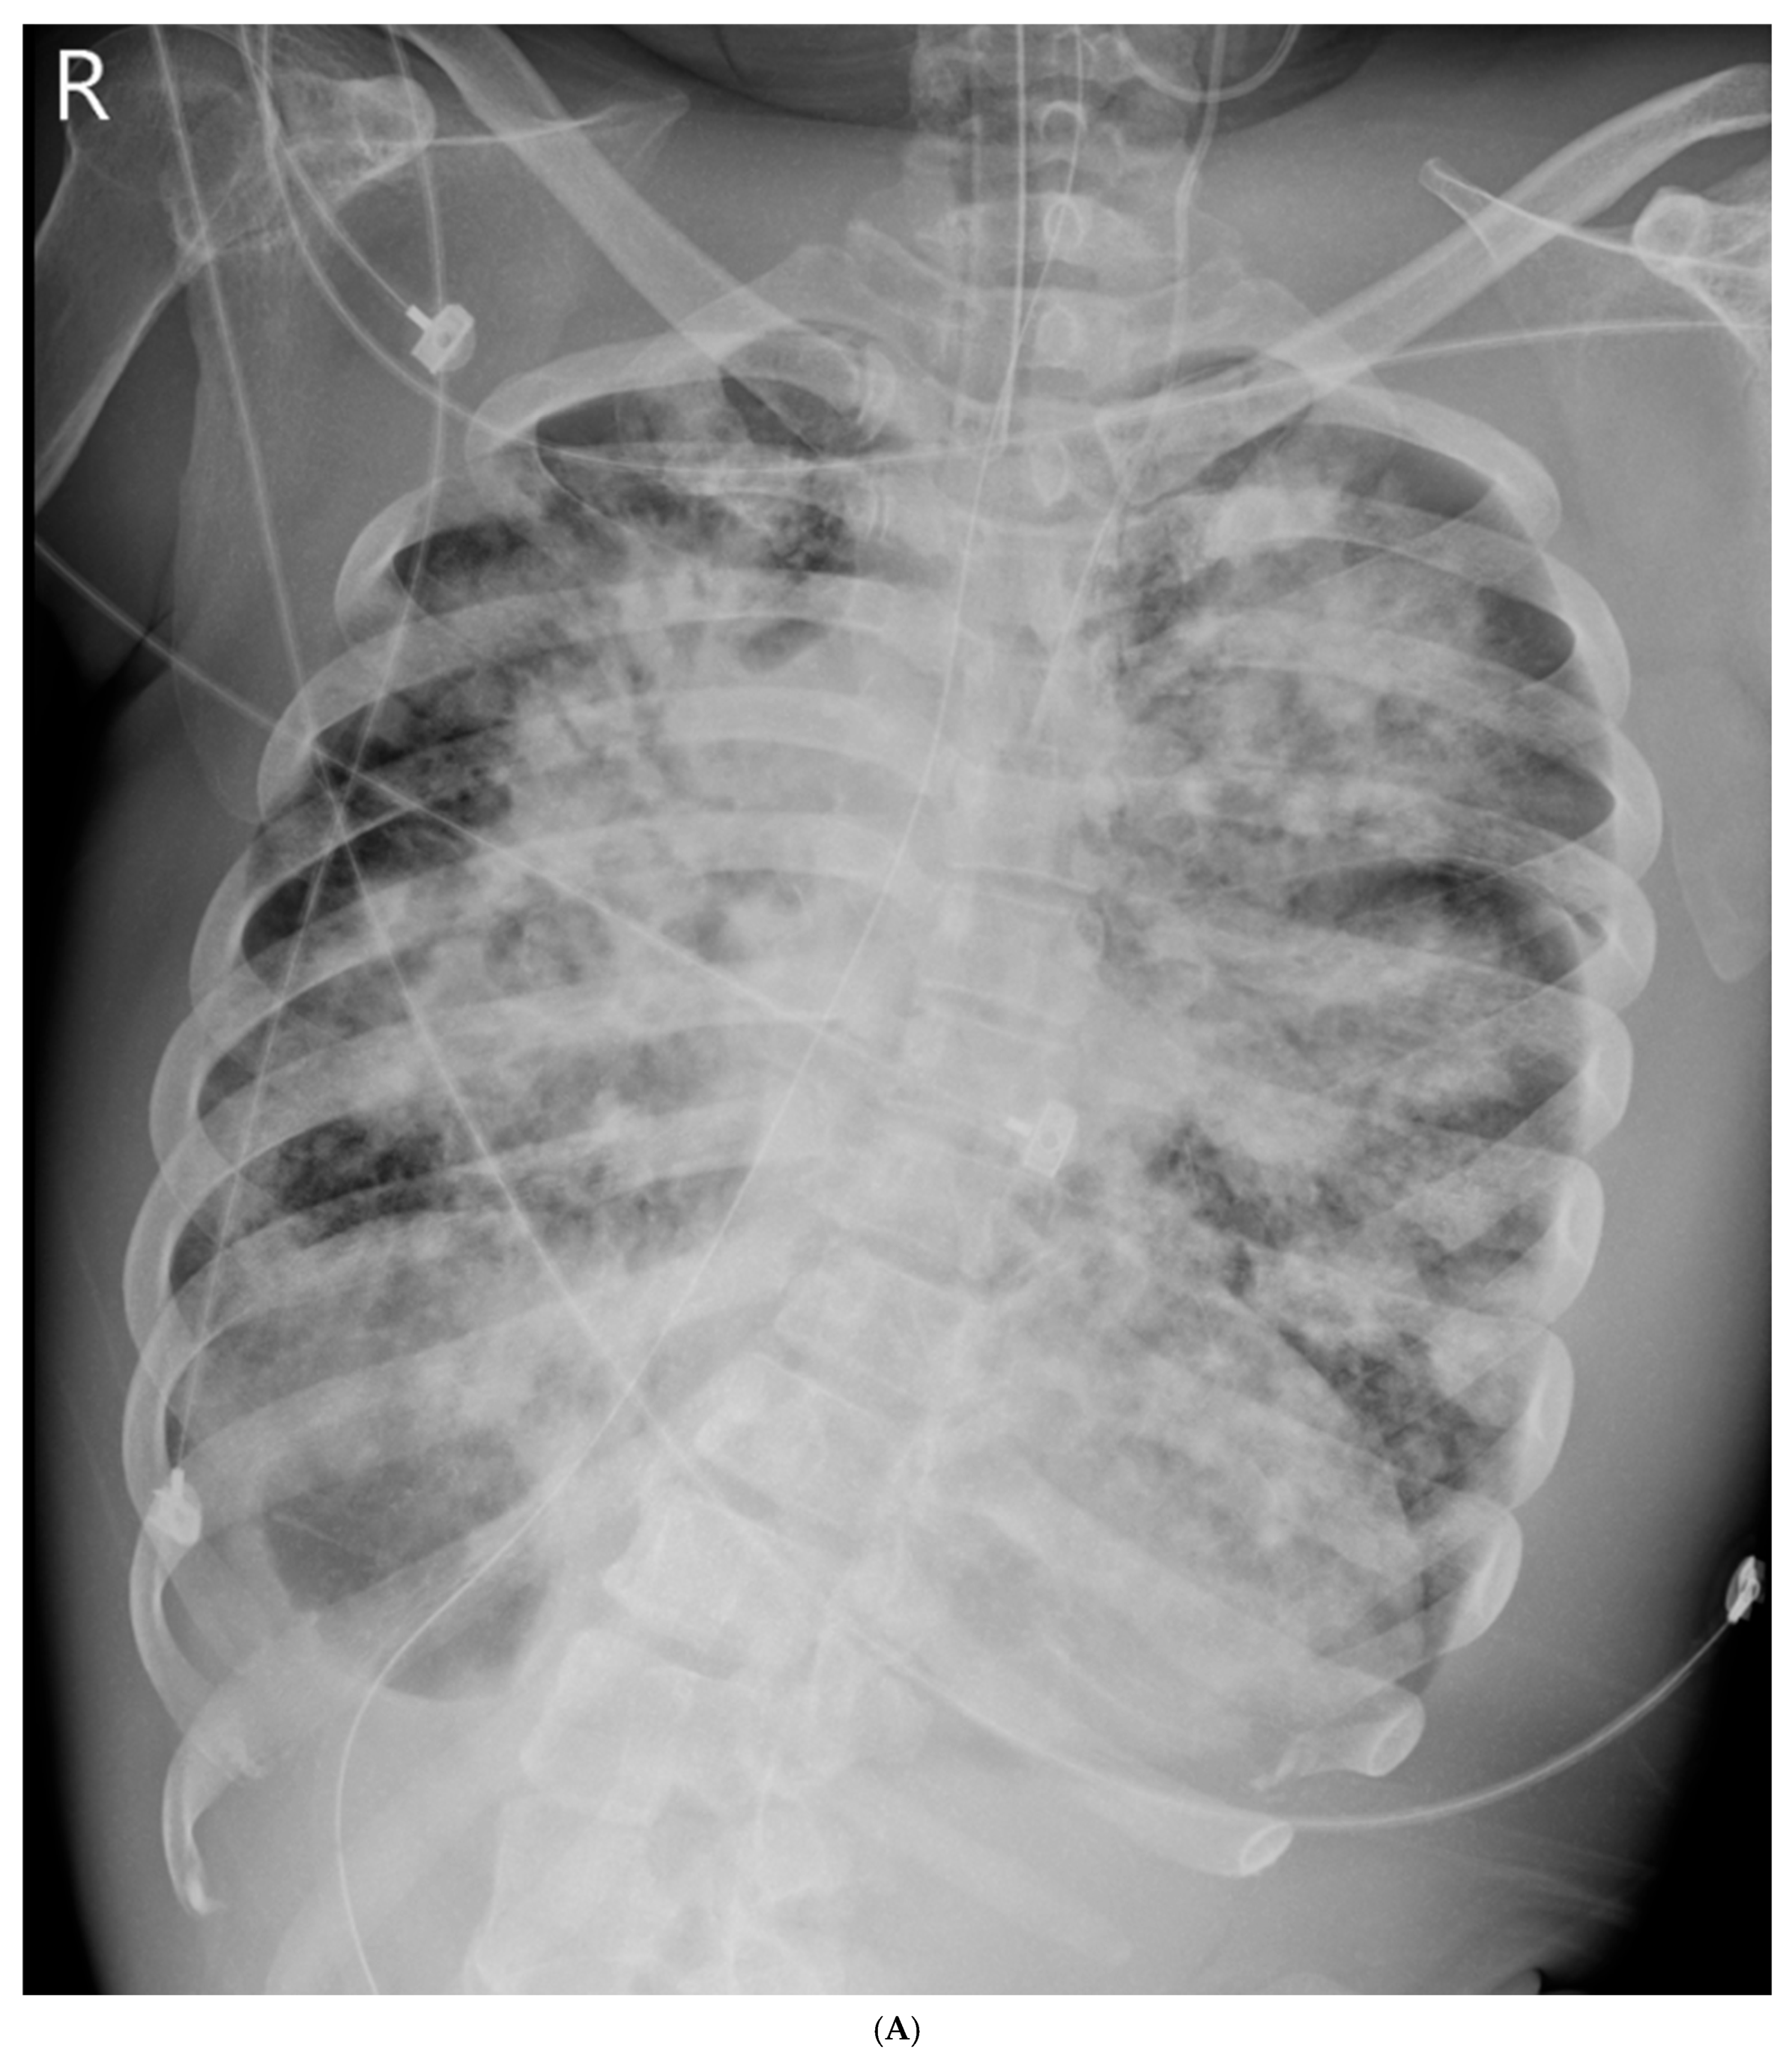

| 0 | Intubation, prone, septic shock | 6.81 | 60 (FiO2 1.0) | 15.5 | 8.1 | None | None | CTX/AZI | No |

| 0 | Intubation, ACLS | MV, Empiric abx, fluid, vasopressor | pH 6.81, P/F 55 |